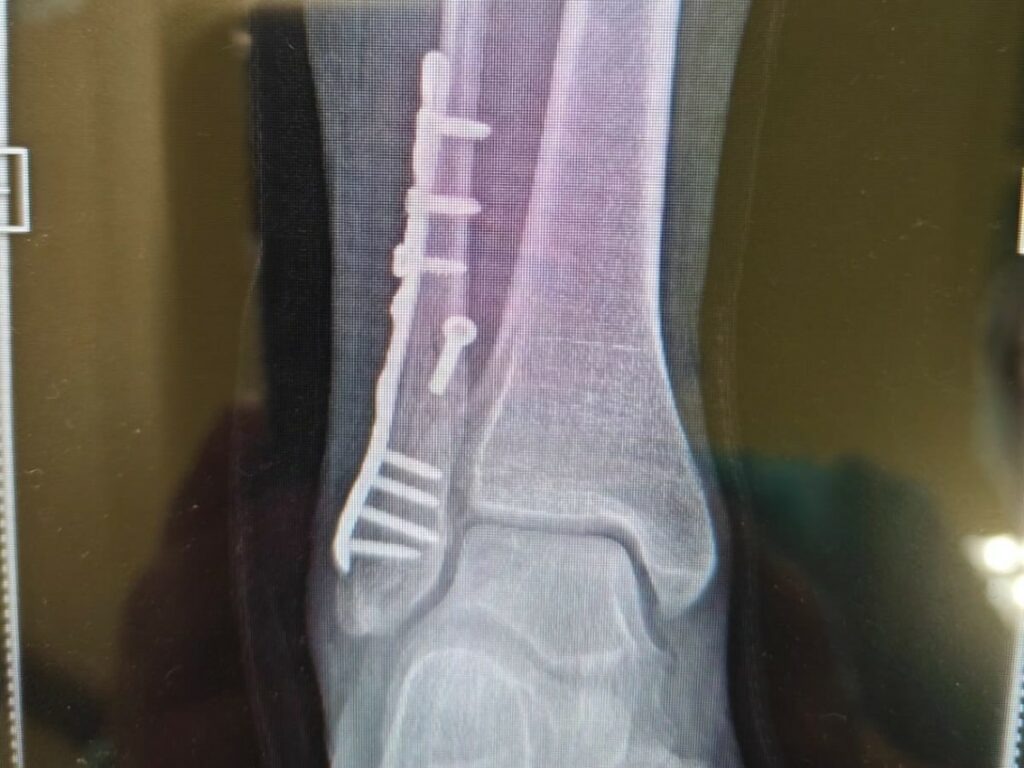

Il primo segnale era arrivato il 26 dicembre, quando Thais si era mostrata con il piede ingessato. Nessuna spiegazione sull’accaduto, solo una frase positiva e una lastra che parlava chiaro: frattura al malleolo peroneale. “Era tutto troppo bello per essere vero”, aveva scritto, sottolineando però di non aver perso il sorriso e di sentirsi fortunata per le persone che aveva accanto.

“Inizierò il mio anno così! Con il piede destro bionico”, ha scritto senza perdere leggerezza. L’intervento è servito a sistemare la frattura con una placca di titanio e alcune viti. L’operazione, assicura lei stessa, è andata benissimo e il recupero è già iniziato. Tra circa venti giorni potrà tornare a camminare, aiutata da un tutore.